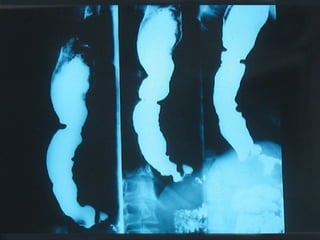

SEGD PATOLOGÍA  ESOFÁGICA A.- Estrechamientos y dilataciones secundarias Acalasia Estenosis Esclerodermia Enf. de Chagas Neoplasia Lesiones por quemadura (cáusticos y dietéticos etc.)